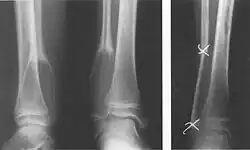

- Einfache (juvenile) Knochenzyste: Das heute etablierte Verfahren ist die intramedulläre Osteosynthese (Prevot-Nagelung) des Knochens. Hierbei wird eine in einigen Fällen entstandene Fraktur stabilisiert, die Knochenzyste erhält gleichzeitig einen Reiz auszuheilen. Einige Gruppen verwenden zur Ausheilung nicht frakturierter juveniler Zysten noch eine Injektion von Cortison-Lösungen oder eine Perforation mit Eröffnung der Zystenwand.